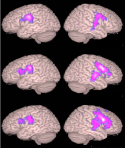

schizophreniaResting MEGI Functional Connectivity in Schizophrenia predicts symptoms.

The goal here is to examine the spatiotemporal dynamics of brain networks involved in speech, language and memory processes. We specifically focus on overt speech production, its interaction with auditory feedback processing, and with language and memory processes. Several recent studies have shown that speaking causes "speaking-induced suppression" or SIS - a suppressed response to self-produced speech when compared to identical speech from an external source - in auditory cortex and associative regions. In our own recent work, we have shown that SIS is present in auditory cortex, and does not result from overall inhibition of auditory cortex during speaking. Rather, SIS results from a comparison between actual auditory input and an internal "speaking-induced prediction" (SIP) of that auditory input. What is the functional significance of SIS and SIP? Based on several lines of evidence, we have developed a conceptual working model for SIS and SIP. The principal goal of this research is to test predictions from this model. Our overall approach capitalizes on unique real-time speech feedback alteration methods developed by our research team, the excellent spatial resolution of functional magnetic resonance imaging (fMRI), the excellent temporal resolution of electromagnetic source imaging (ESI) and advanced analyses methods that we have developed for reconstructing spatiotemporal dynamics and connectivity of distributed cortical networks.